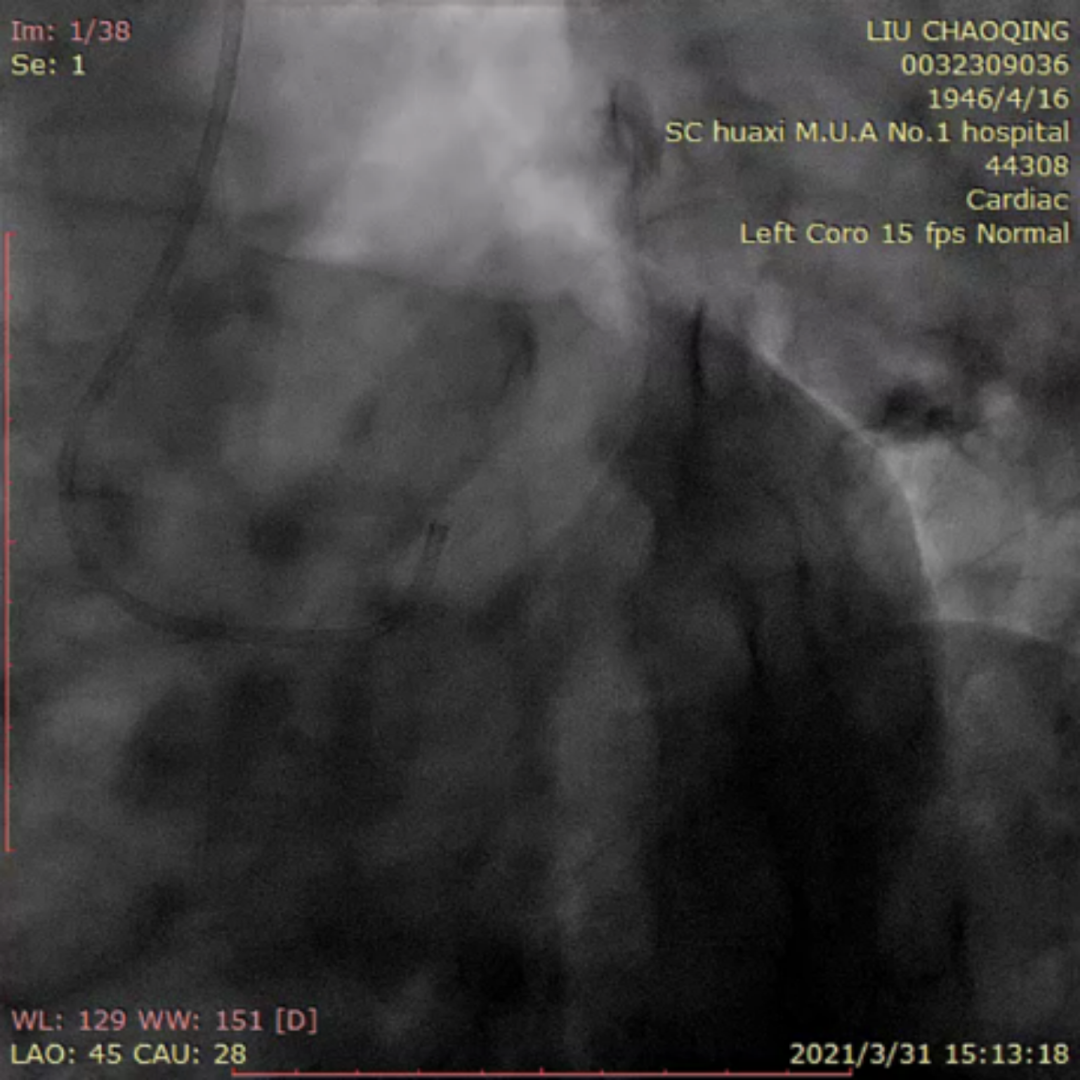

来自四川大学华西医院的李晨教授为大家分享了一例ADR开通前降支CTO的疑难病例。患者为老年男性,反复活动后胸痛6月。当地医院冠脉造影提示前降支完全闭塞,尝试PCI未能成功开通血管。予规范药物治疗,患者仍反复有胸痛入院。患者两段CTO,闭塞段长,钙化重,成角,前次失败,J-CTO 4分,右窦上方侧枝供应间隔-前降支;回旋支自身侧枝供应对角支;右冠无明显侧枝;前降支中段着陆区条件较好,ADR着陆区条件尚可。

前降支开口完全闭塞,似见残端

前降支近段可见岛状显影伴钙化

岛状显影处似与对角支相连;但造影剂消散慢,不排除假腔未愈合

前降支中远段可见自身逆向侧枝

右冠窦上方侧枝供应前降支

右窦造影显示侧枝较扭曲

双侧造影:右冠侧枝条件差,自身侧枝供应对角支

患者术中遭遇前降支导丝受阻,对侧和同侧造影前降支远端显影不清的问题。后双侧造影时可见对角支和前降支主支相通。同侧逆向可清晰显示对角支,若进入对角支真腔,可调整方向或通过KDL将导丝放入前降支。随后Pilot 200顺利进入对角支,导丝进入对角支分支。然而随后导丝在第二段闭塞重度钙化处进入假腔,从假腔进入对角支,在远端重回真腔。后启动ADR。最后李晨教授结合病例对逆向及ADR启动时机和ADR穿刺位点选择进行了发表了个人见解。